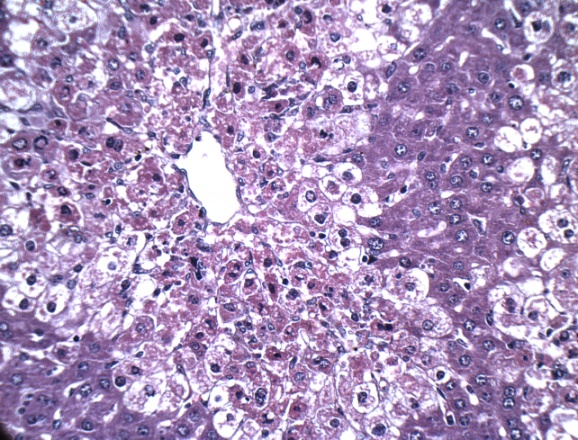

Histopathology

Histological profile of the normal control group revealed normal histology of liver with central vein, hepatocytes and portal triads. MTX induced group revealed marked degree of centrilobular necrosis along with polymorphonuclear cells infiltration, severe vacuolations in the hepatocytes and sinusoidal congestion. Pre-treatment with LIV-52 reduced MTX induced microscopic changs and showed marked beneficial effects in the liver architecture. Ambrex treatment at the low dose showed moderate degree of necrosis, mild degree of vacuolations in the hepatocytes with minimal sinusoidal congestion. Ambrex administration at high dose revealed regeneration of hepatocytes to normal architecture, absence of sinusoidal congestion and vacuolations in the hepatocytes. On the basis of the above observation, it is concluded that pre-treatment with Ambrex at high dose (500 mg/kg b. wt. p. o) have hepatoprotective activity against MTX induced hepatotoxicity (fig. 4).

A B

C D

E

Fig. 4: Representative photograph showing the effect of Ambrex on MTX induced mice liver-H & E stain X400 magnification. (A) Normal control, (B) Positive control (C) MTX+LIV 52, (D) MTX+Ambrex (250 mg/kg b. wt., p. o.) and (E) MTX+Ambrex (500 mg/kg b. wt., p. o.) treated group